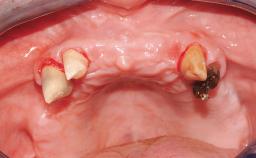

ITI Curriculum FL: Patient Assessment Case 7

Example intended for case-based discussion regarding patient assessment, diagnosis and determination of risk and complexity.

| Case Type | Short Space |

| Jaw | Maxilla |

| Area | Posterior |

| # of Teeth | 2 |